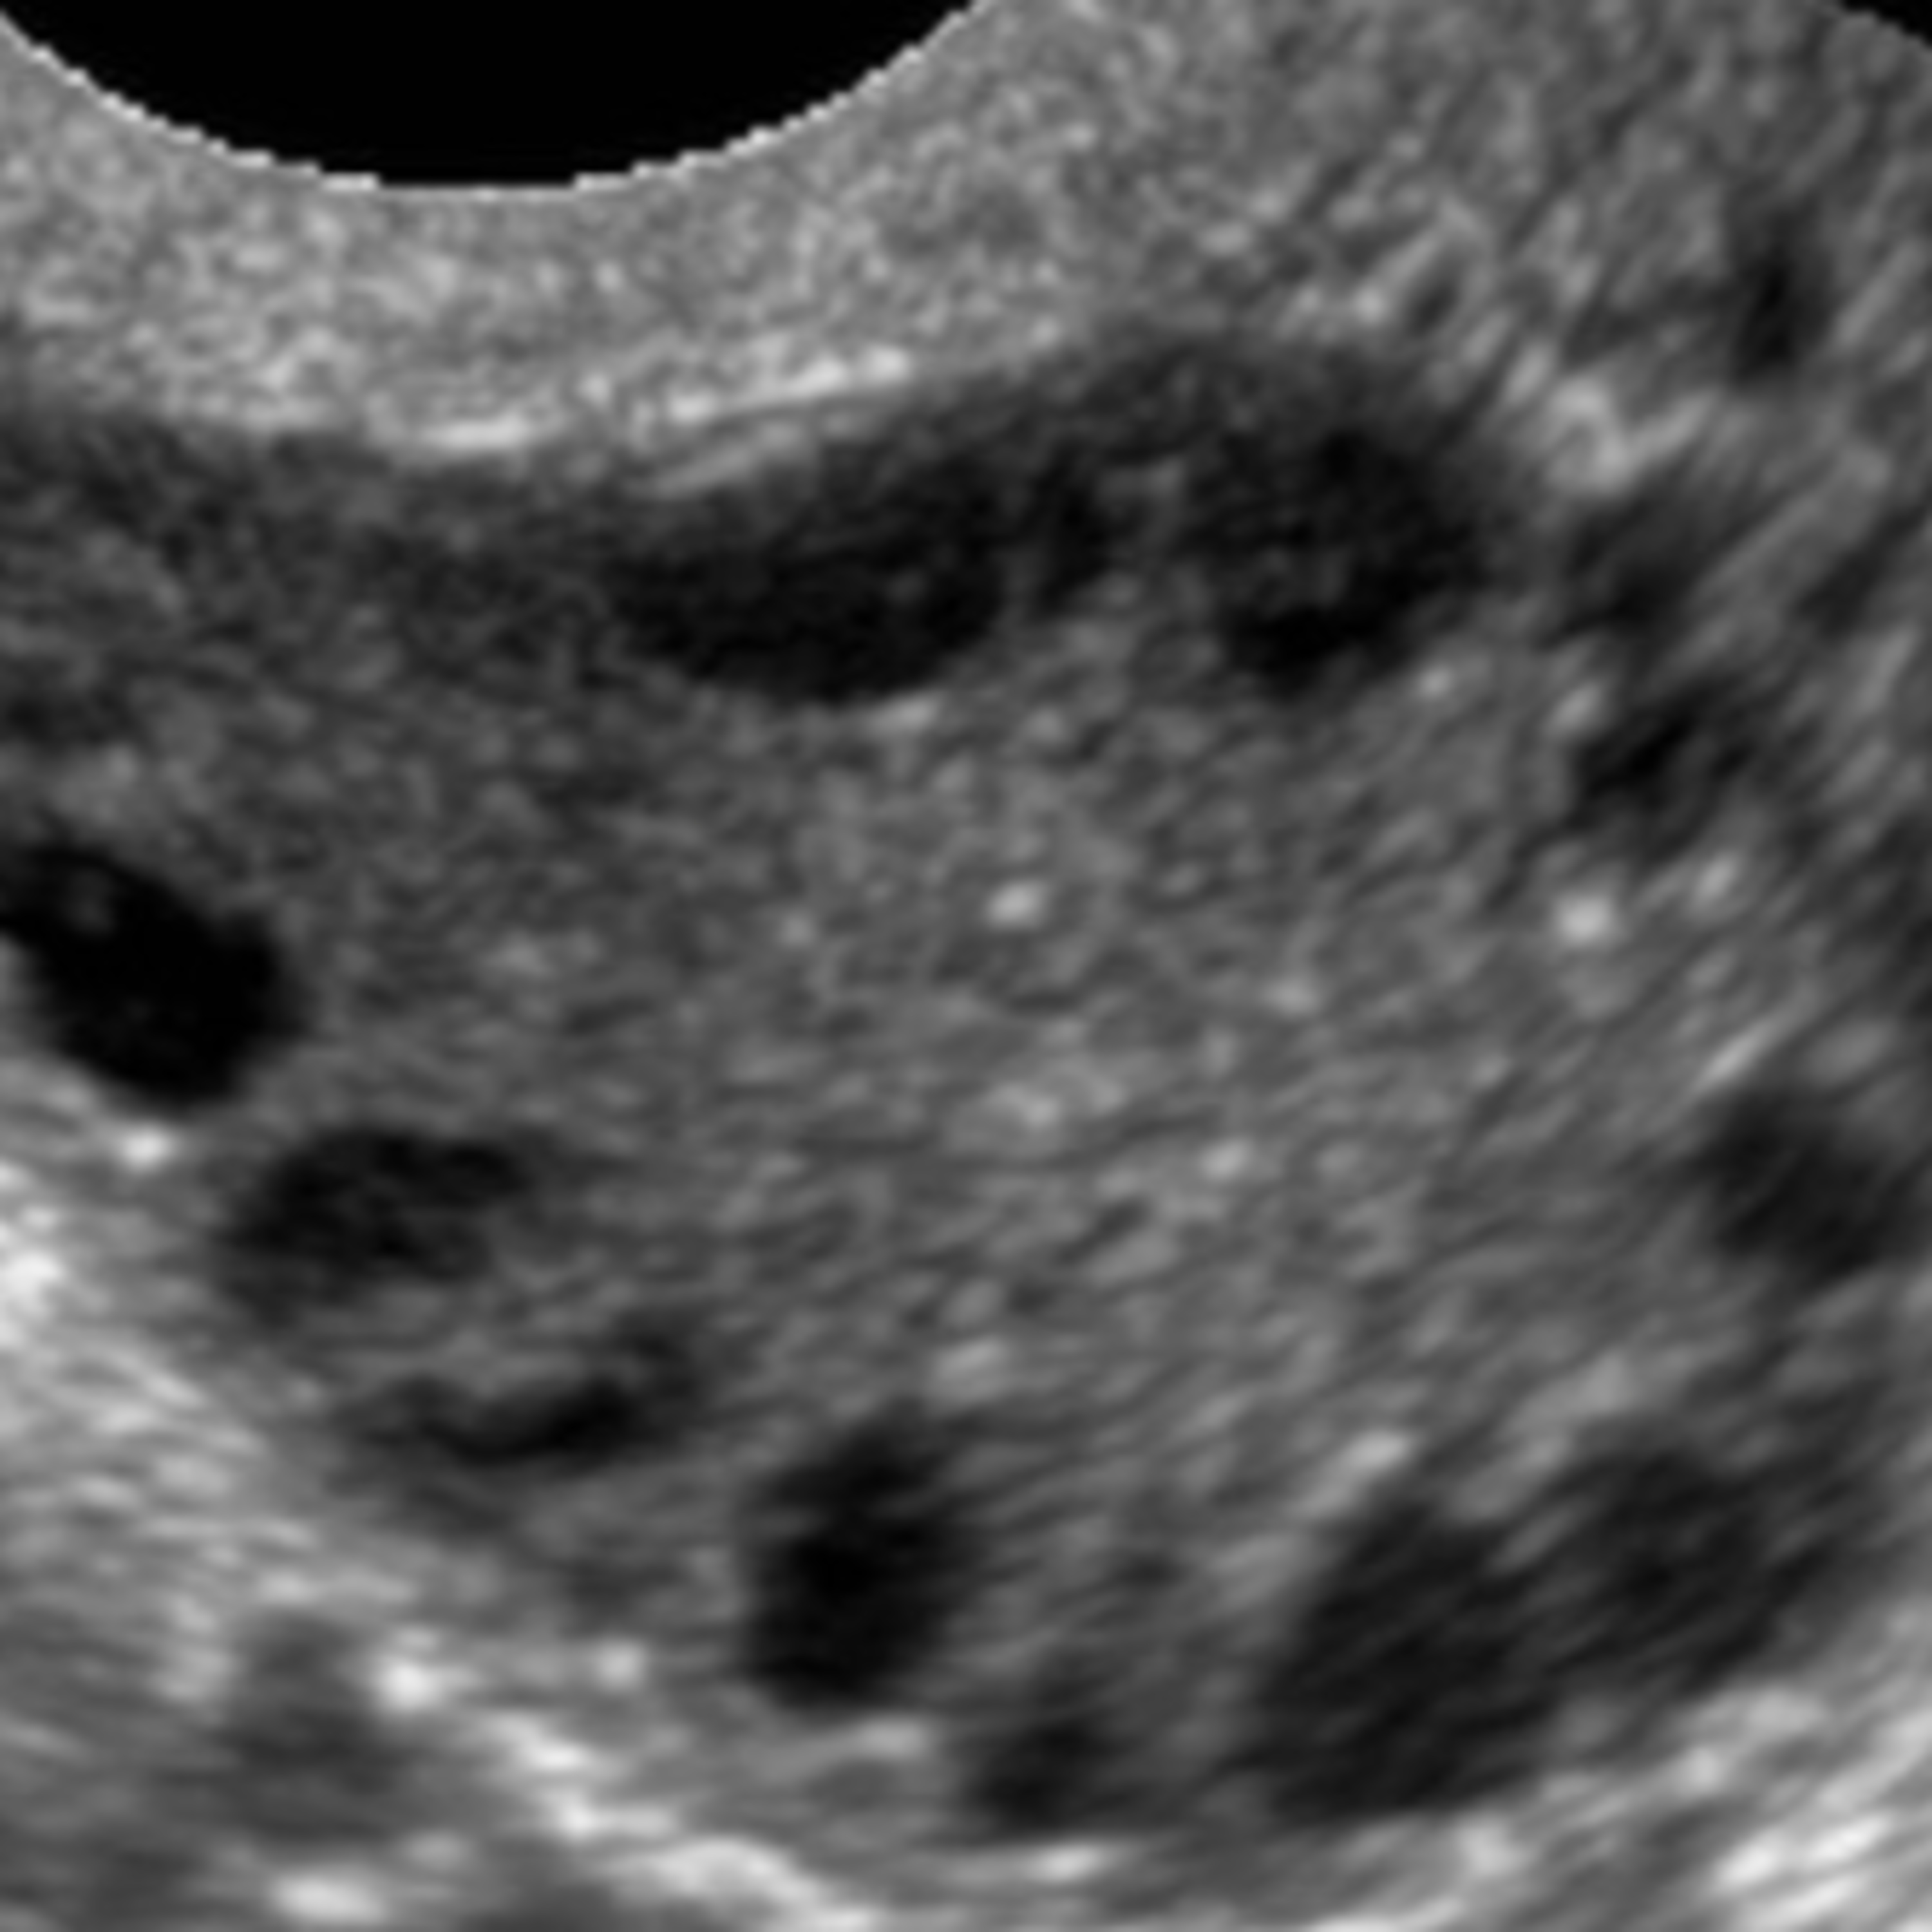

Um importante tema em Infertilidade é discutido pelos médicos especialistas Paula Marin e Sergio Gonçalves: a SÍNDROME DOS OVÁRIOS POLICÍSTICOS (SOP). Entenda o que é a SOP, quando ela deve ser investigada e quais são os critérios necessários para o seu diagnóstico.